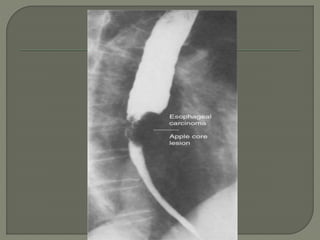

A barium esophagram is recommended

for any patient presenting with

dysphagia

is able to differentiate intraluminal from

intramural lesions and to discriminate

between intrinsic (from a mass

protruding into the lumen) and extrinsic

(from compression of a structures

outside the esophagus) compression

The classic finding of an apple-core

lesion in patients with esophageal

cancer is recognized easily

Although the esophagram will not be

specific for cancer, it is a good first test

to perform in patients presenting with

dysphagia and a suspicion of

esophageal cancer